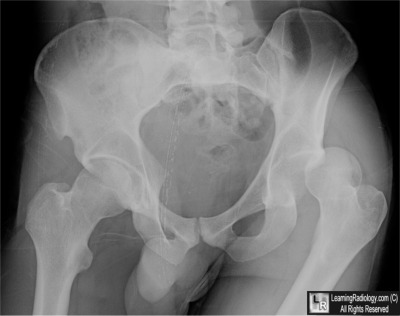

Case of the Week 522

What is the most likely diagnosis?

• 37 year-old in motor vehicle accident

Frontal Radiograph of Pelvis

4. Posterior Hip Dislocation

Posterior Hip Dislocation

• Hip dislocation accounts for only 5% of all dislocations

• Posterior hip dislocations are much more common than anterior hip dislocations (90% to about 10%)

• Mechanism in posterior dislocation classically is unrestrained occupant of a motor vehicle accident, especially collisions which are head-on, in which the flexed knee strikes dash with hip flexed and adducted

• Force is transmitted from the foot or ankle along femoral shaft to the hip

• Associated with fractures of the posterior rim of the acetabulum